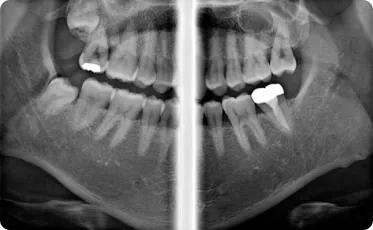

Технологии Ray обеспечивают самое лучшее качество и высокую чёткость панорамных снимков

Байт-Винг

Ортогональный